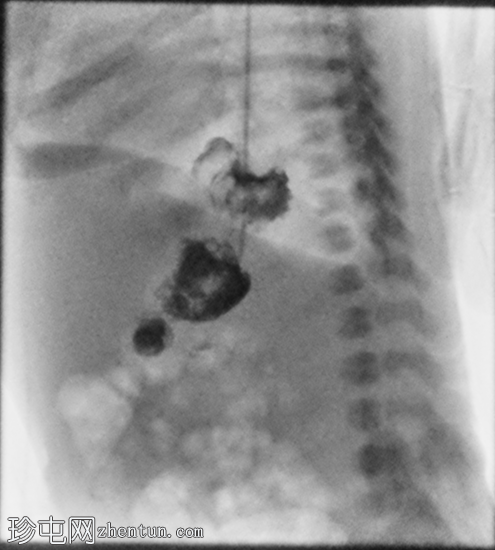

足月新生儿无法耐受任何喂养,经胃管/口服喂养后出现大量呕吐。评估是否存在肠旋转不良和胃排空障碍。

X线片

正位

胃部初始显影,并立即反流至食管裂孔疝。在其近端可见管径正常的远端食管。十二指肠降部和横部显影较弱,左上腹可见数段管径较小/部分减压的近端小肠显影。

延迟1小时拍摄的X线片显示食管裂孔疝和胃部仍有造影剂残留,造影剂远端扩散受限,很可能是由于造影剂用量较少所致。充满气体的肠袢外观正常,乙状结肠内可见气体,直肠内未见气体。

这是一例儿童患者在透视下发现的食管裂孔疝病例。

最初的临床考虑是肠旋转不良,因为患者频繁且呕吐量大,但后来怀疑这是由中等大小的食管裂孔疝引起的。